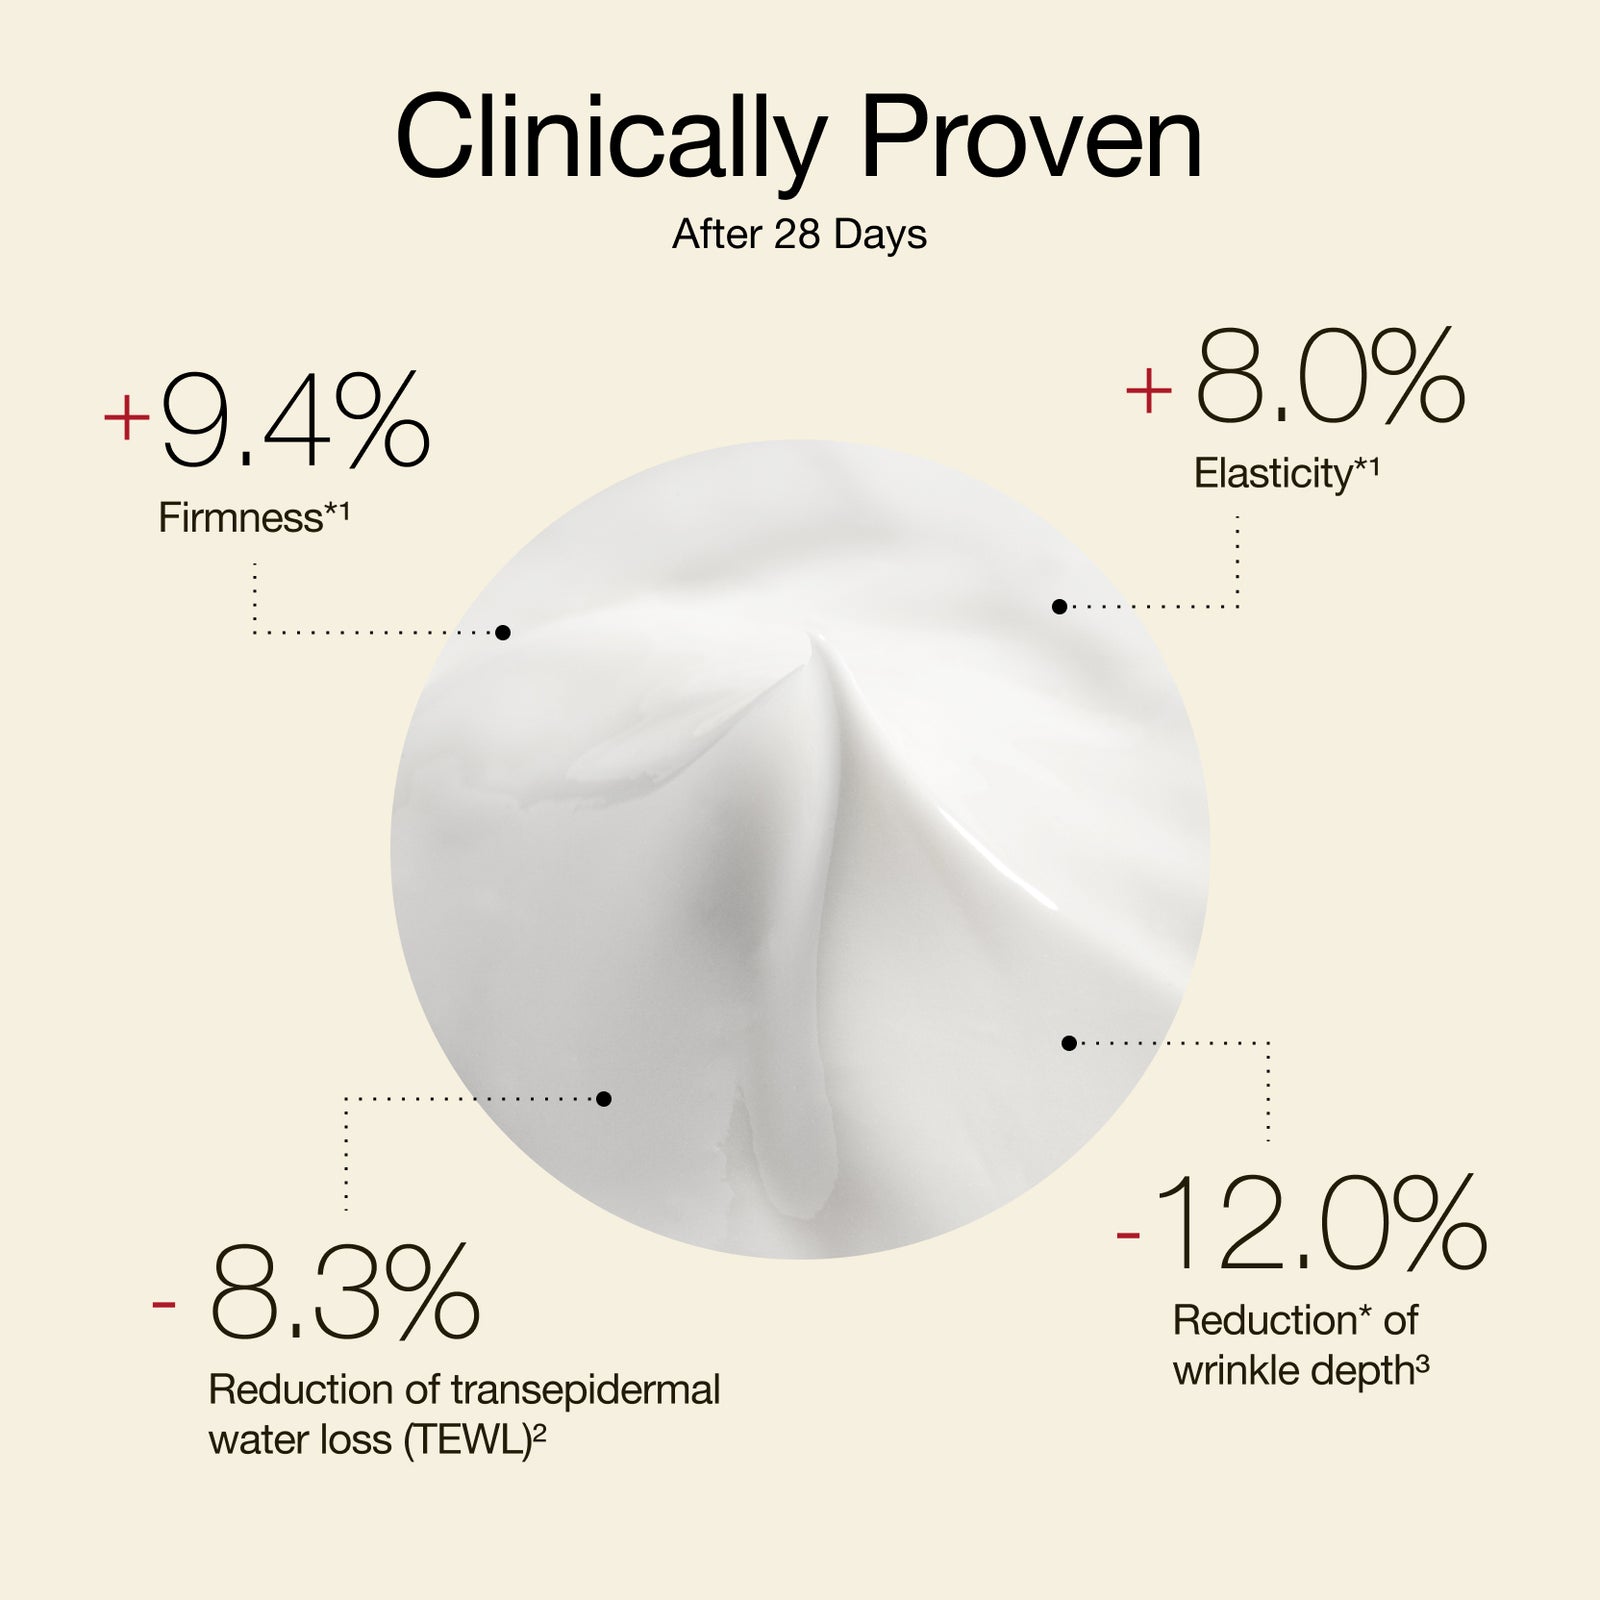

THE RESULTS ARE ULTRA REMARKABLE*

- 100% said skin felt moisturized

- 100% said skin looked smoother

- 97% saw visible improvement in firmness

- 97% said skin was intensely revitalized

- 93% said their skin complexion looked even

*Independent consumer study on 30 participants over 28 days of usage.